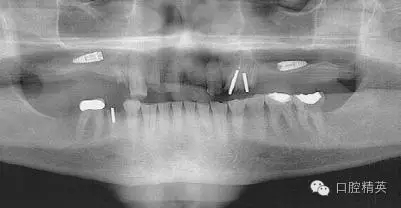

圖1a:術后根尖片顯示種植體傳入左側(cè)上頜竇

我們通過文獻和網(wǎng)站檢索獲得了一些關于種植體失敗的研究和綜述文章。一個和僅使用兩維放射診斷(根尖片或曲斷片)有關的常見失敗是上頜竇穿孔。(圖1a-c)通常牙醫(yī)由于錯誤的估計了上頜竇底骨量高度而造成幾個毫米的上頜竇底穿孔。一些病例可能沒有癥狀,象圖中所示的這個病例,患者需要嚴格的監(jiān)控、復查。有些病例則出現(xiàn)并發(fā)癥,種植體不得不取出。